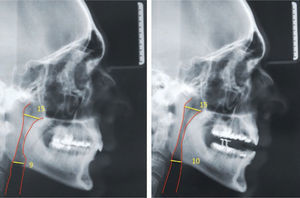

Casos clínicosSe muestran 2 pacientes que utilizaron un dispositivo de avance mandibular de diseño nacional, hecho en laboratorio Ortolab, durante 1 mes, donde previo y posterior al uso de este aparato se mide el índice de Apnea e Hipoapnea, ronquidos y saturación de oxígeno con el Apnealink®, de la empresa Resmed. Cada paciente presenta una polisomnografía inicial, 2 telerradiografías de perfil (con y sin el dispositivo) y distintos cuestionarios, Escala de Epworth, Escala de Thornton del sueño y Observador del sueño, respondidos antes y después del tratamiento.